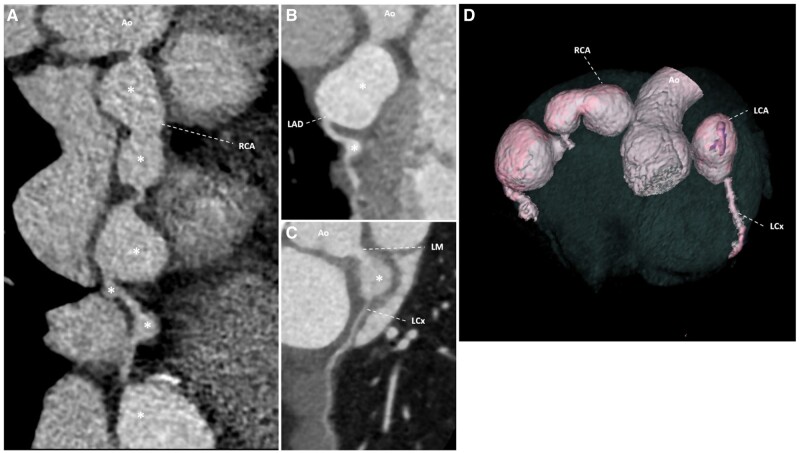

Kawasaki disease is the most common vasculitis causing acquired coronary artery aneurysm (CAA) and affects mostly children. Computed tomography coronary angiography (CTCA) has unique diagnostic and prognostic values in cases of giant CAA. Here, we report technical challenges encountered when performed CTCA for a case of Kawasaki disease complicated with giant CAA. In particular, there was significant flow alteration caused by the giant CAA(s) causing suboptimal enhancement when the standard protocol was applied. We share our experience in optimizing the scan and propose the use of either manual bolus tracking or test bolus technique in similar scenarios, as well as multidisciplinary approach to optimize patient preparation.